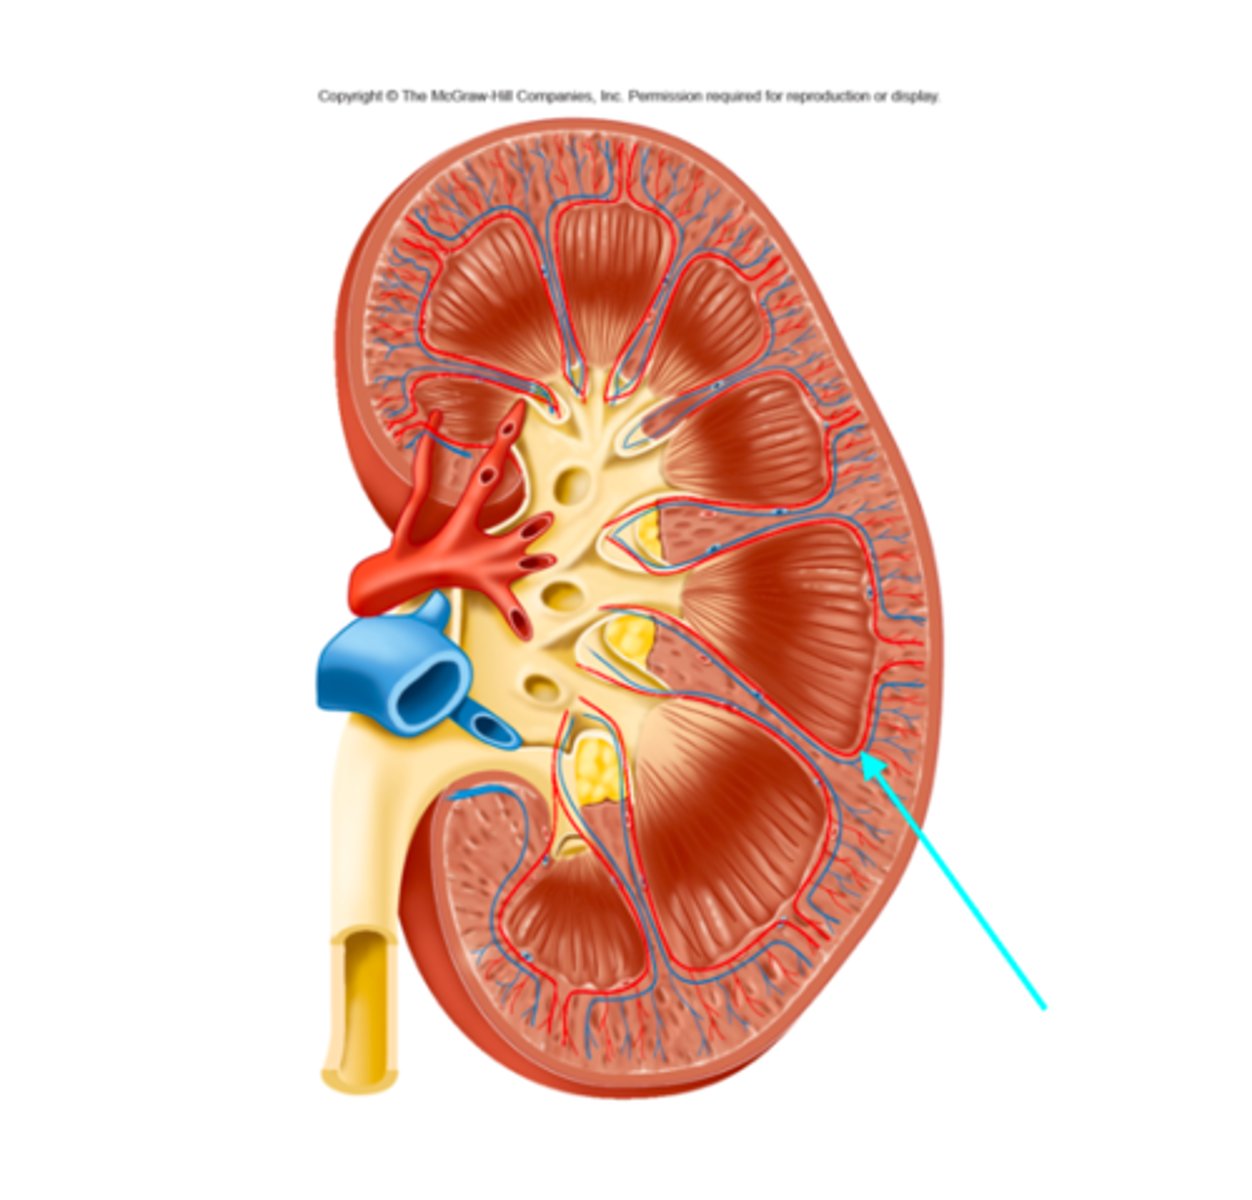

What structure of the kidneys is the blue arrow pointing at?

Arcuate arteries and veins

What structures of the kidneys are located where the blue arrow is pointing?